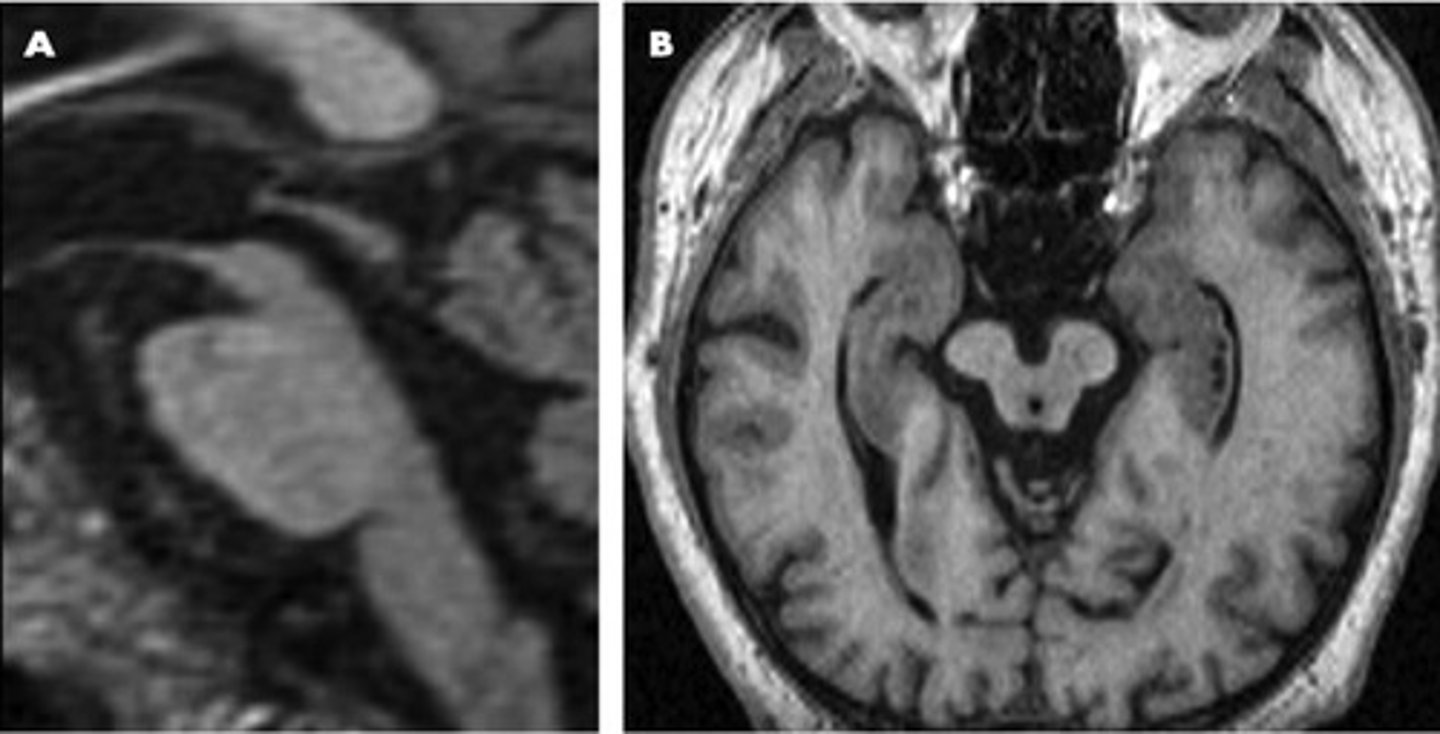

Alzheimer's disease

a progressive and irreversible brain disorder characterized by gradual deterioration of memory, reasoning, language, and, finally, physical functioning

cortical atrophy

death of cells in the cerebral cortex

amyloid plaques

fragments of the protein beta-amyloid that accumulate into insoluble plaques that inhibit communication between neurons

beta-amyloid

a protein that accumulates in amyloid plaques in Alzheimer's disease

neurofibrillary tangles

spiral-shaped masses formed when fibers that compose the axon become twisted together